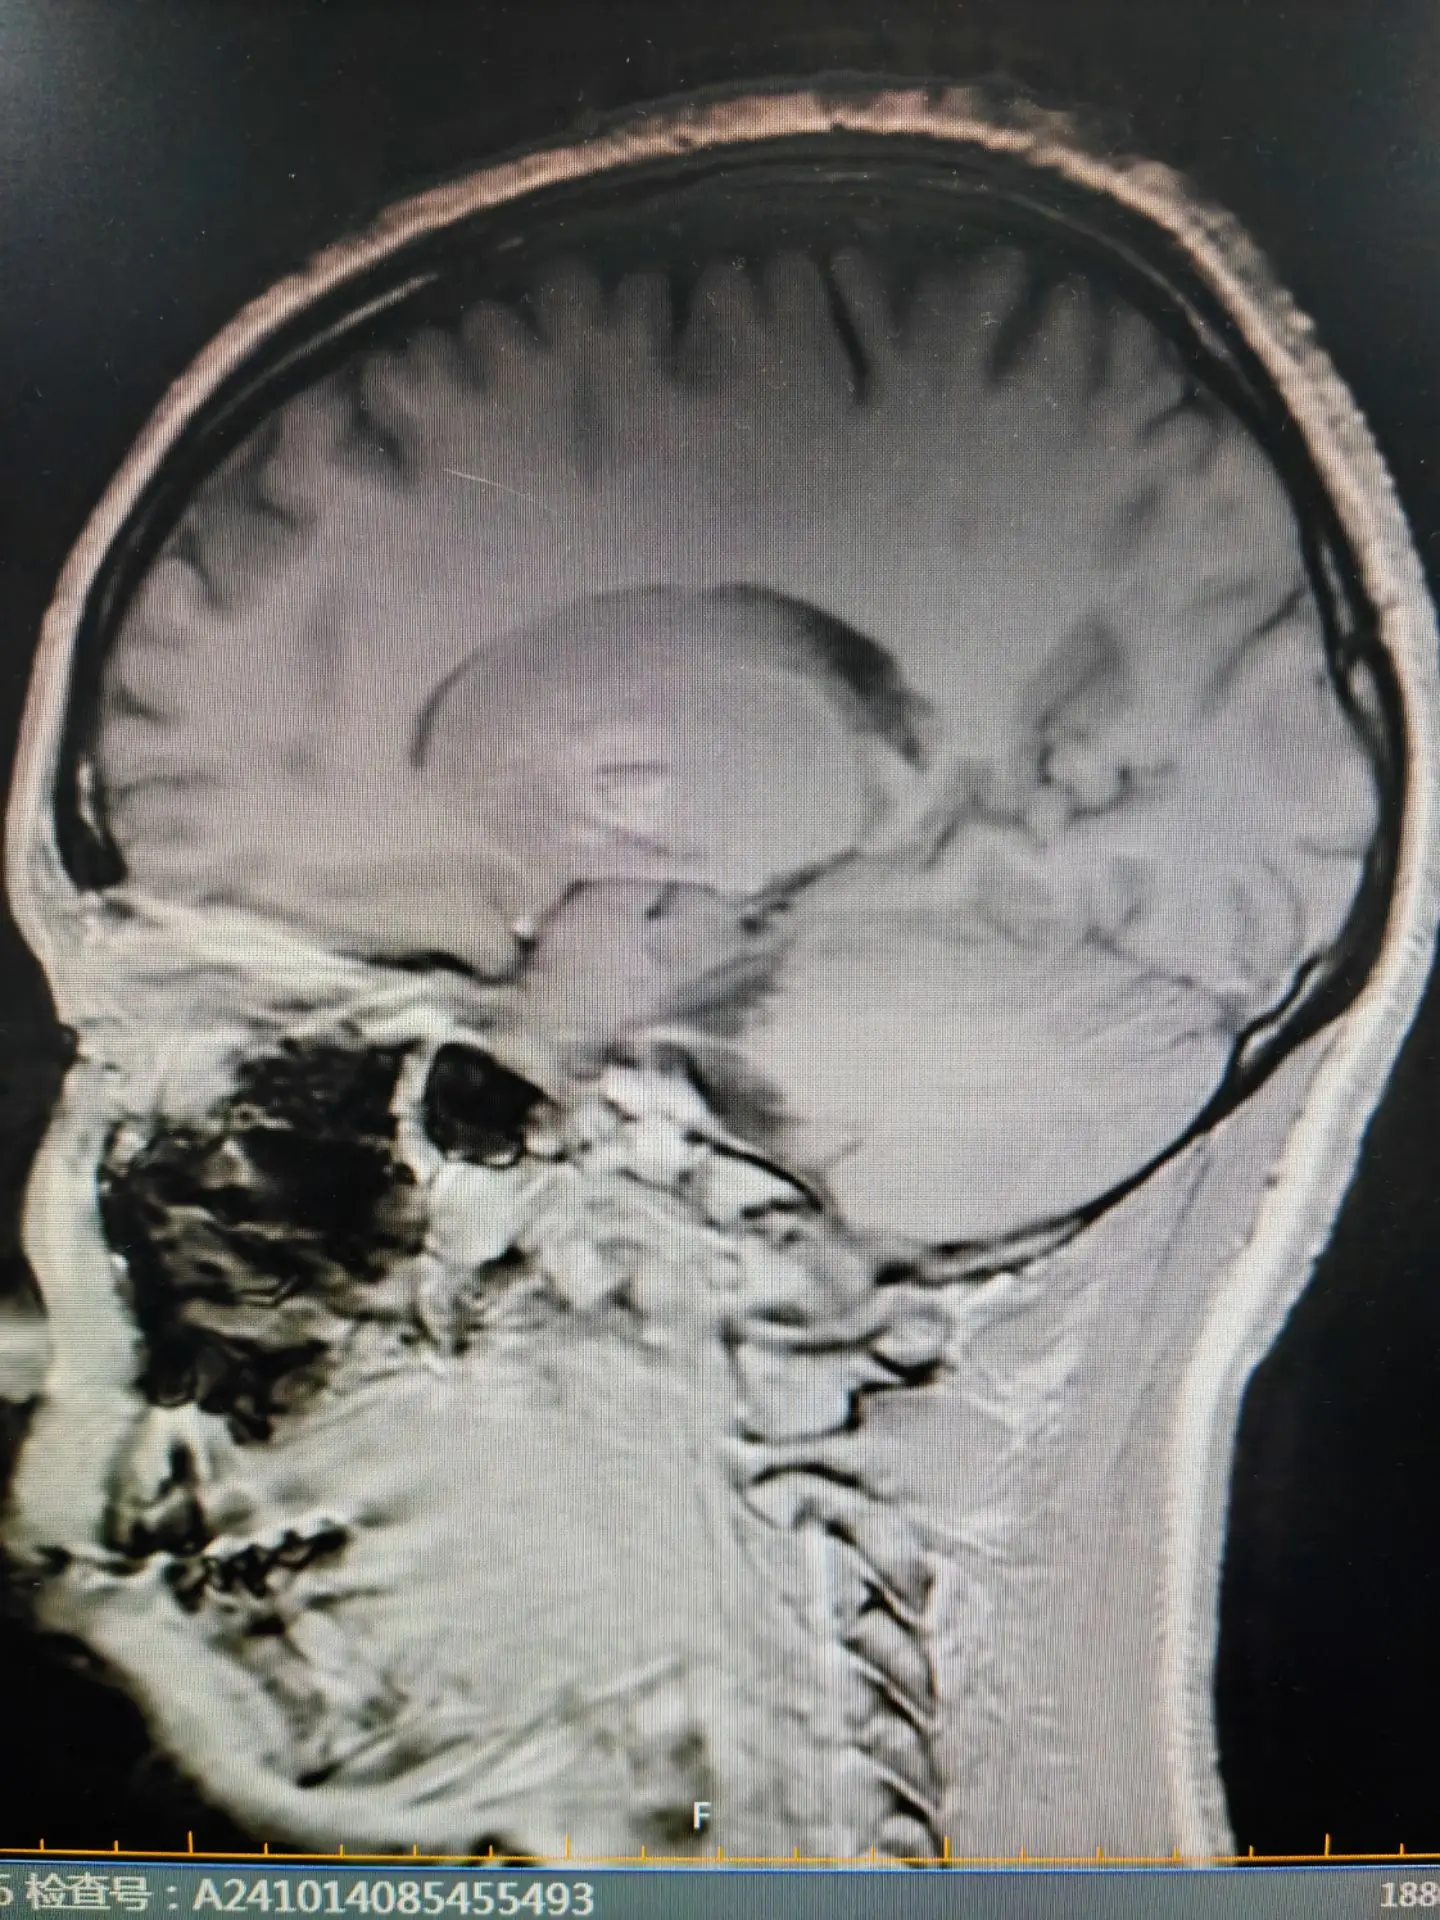

脑铁沉积病—虎眼征👁。脑铁沉积病目前发现有10种不同的基因遗传相关的神经系统退行性疾病,常伴有基底节区的铁沉积,其中有7种脑铁沉积病可表现为PPS。尤其最为常见的PANK2基因突变引起的泛酸激酶相关性神经退行性疾病,青少年起病,首发症状可表现为帕金森样表现,合并锥体束征和认知精神障碍,头核磁可表现为典型的“虎眼”征。脑铁沉积病的患者其帕金森症状对于左旋多巴类药物反应较差或无反应,头核磁表现为不同程度的铁沉积是鉴别的要点。虎眼征